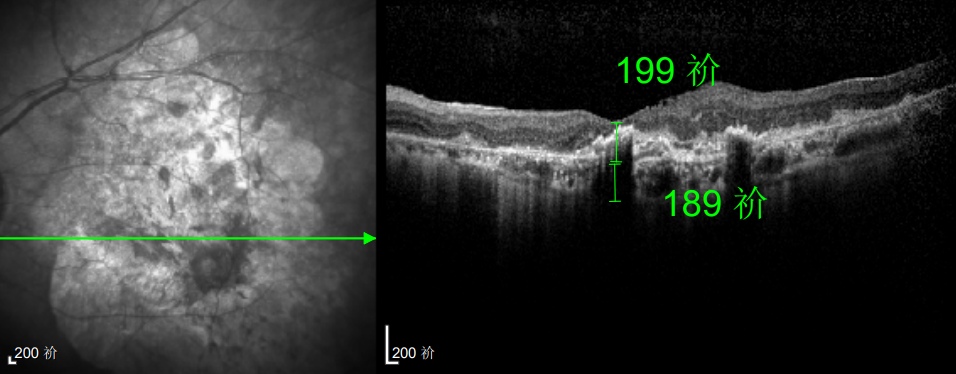

△延誤復(fù)查后的左眼

抗VEGF治療:規(guī)范隨訪,拒絕僥幸

這次教訓(xùn)讓林婆婆徹底醒悟,此后她嚴(yán)格遵照王曉波主任的醫(yī)囑,定期隨訪、規(guī)范治療,再也不敢有絲毫懈怠。雖然左眼視力最終僅恢復(fù)至0.3,但穩(wěn)定的視力狀態(tài)讓她格外珍惜。

黃斑變性

△規(guī)劃化治療后的左眼